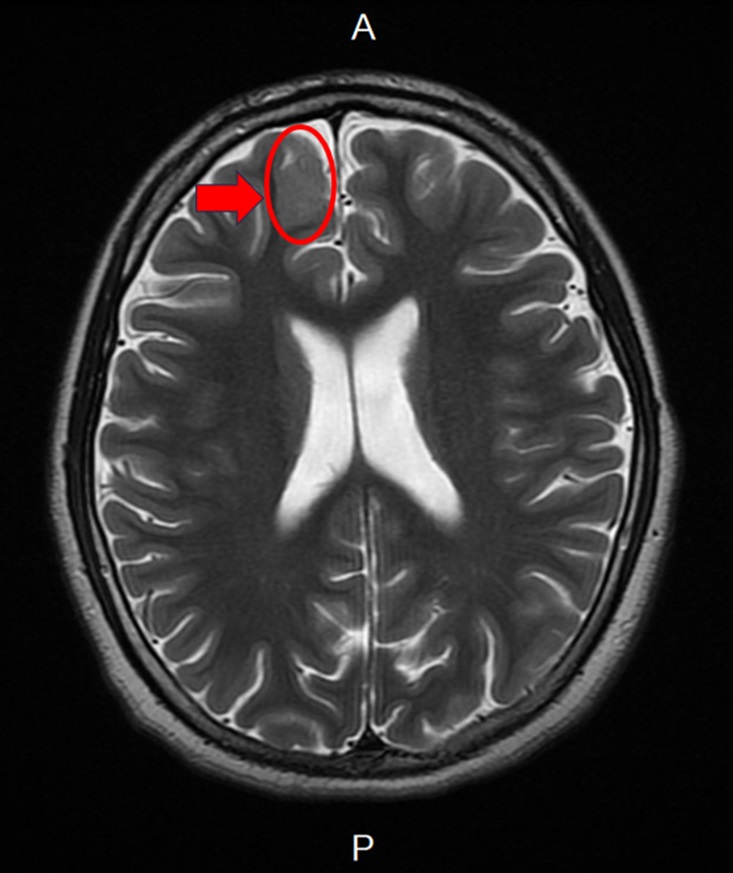

張寶玲醫師診察發現男孩有腦皮質發育不良(如箭頭所示),提醒頑固型癲癇患者應積極與醫師討論評估,除腦部影像外,也可考慮基因檢查,以利個人化精準治療,才能有效控制癲癇。(台大新竹分院提供)

新竹台大分院小兒部張寶玲醫師評估後發現,男孩腦波檢查出現頻繁右側額葉局部癲癇波,懷疑可能存在腦部病灶,進一步安排腦部磁振造影檢查後,發現右側額葉異常病灶,由於病人屬於頑固性癲癇,在多種抗癲癇藥物治療下仍持續發作,醫療團隊評估後建議接受癲癇手術。